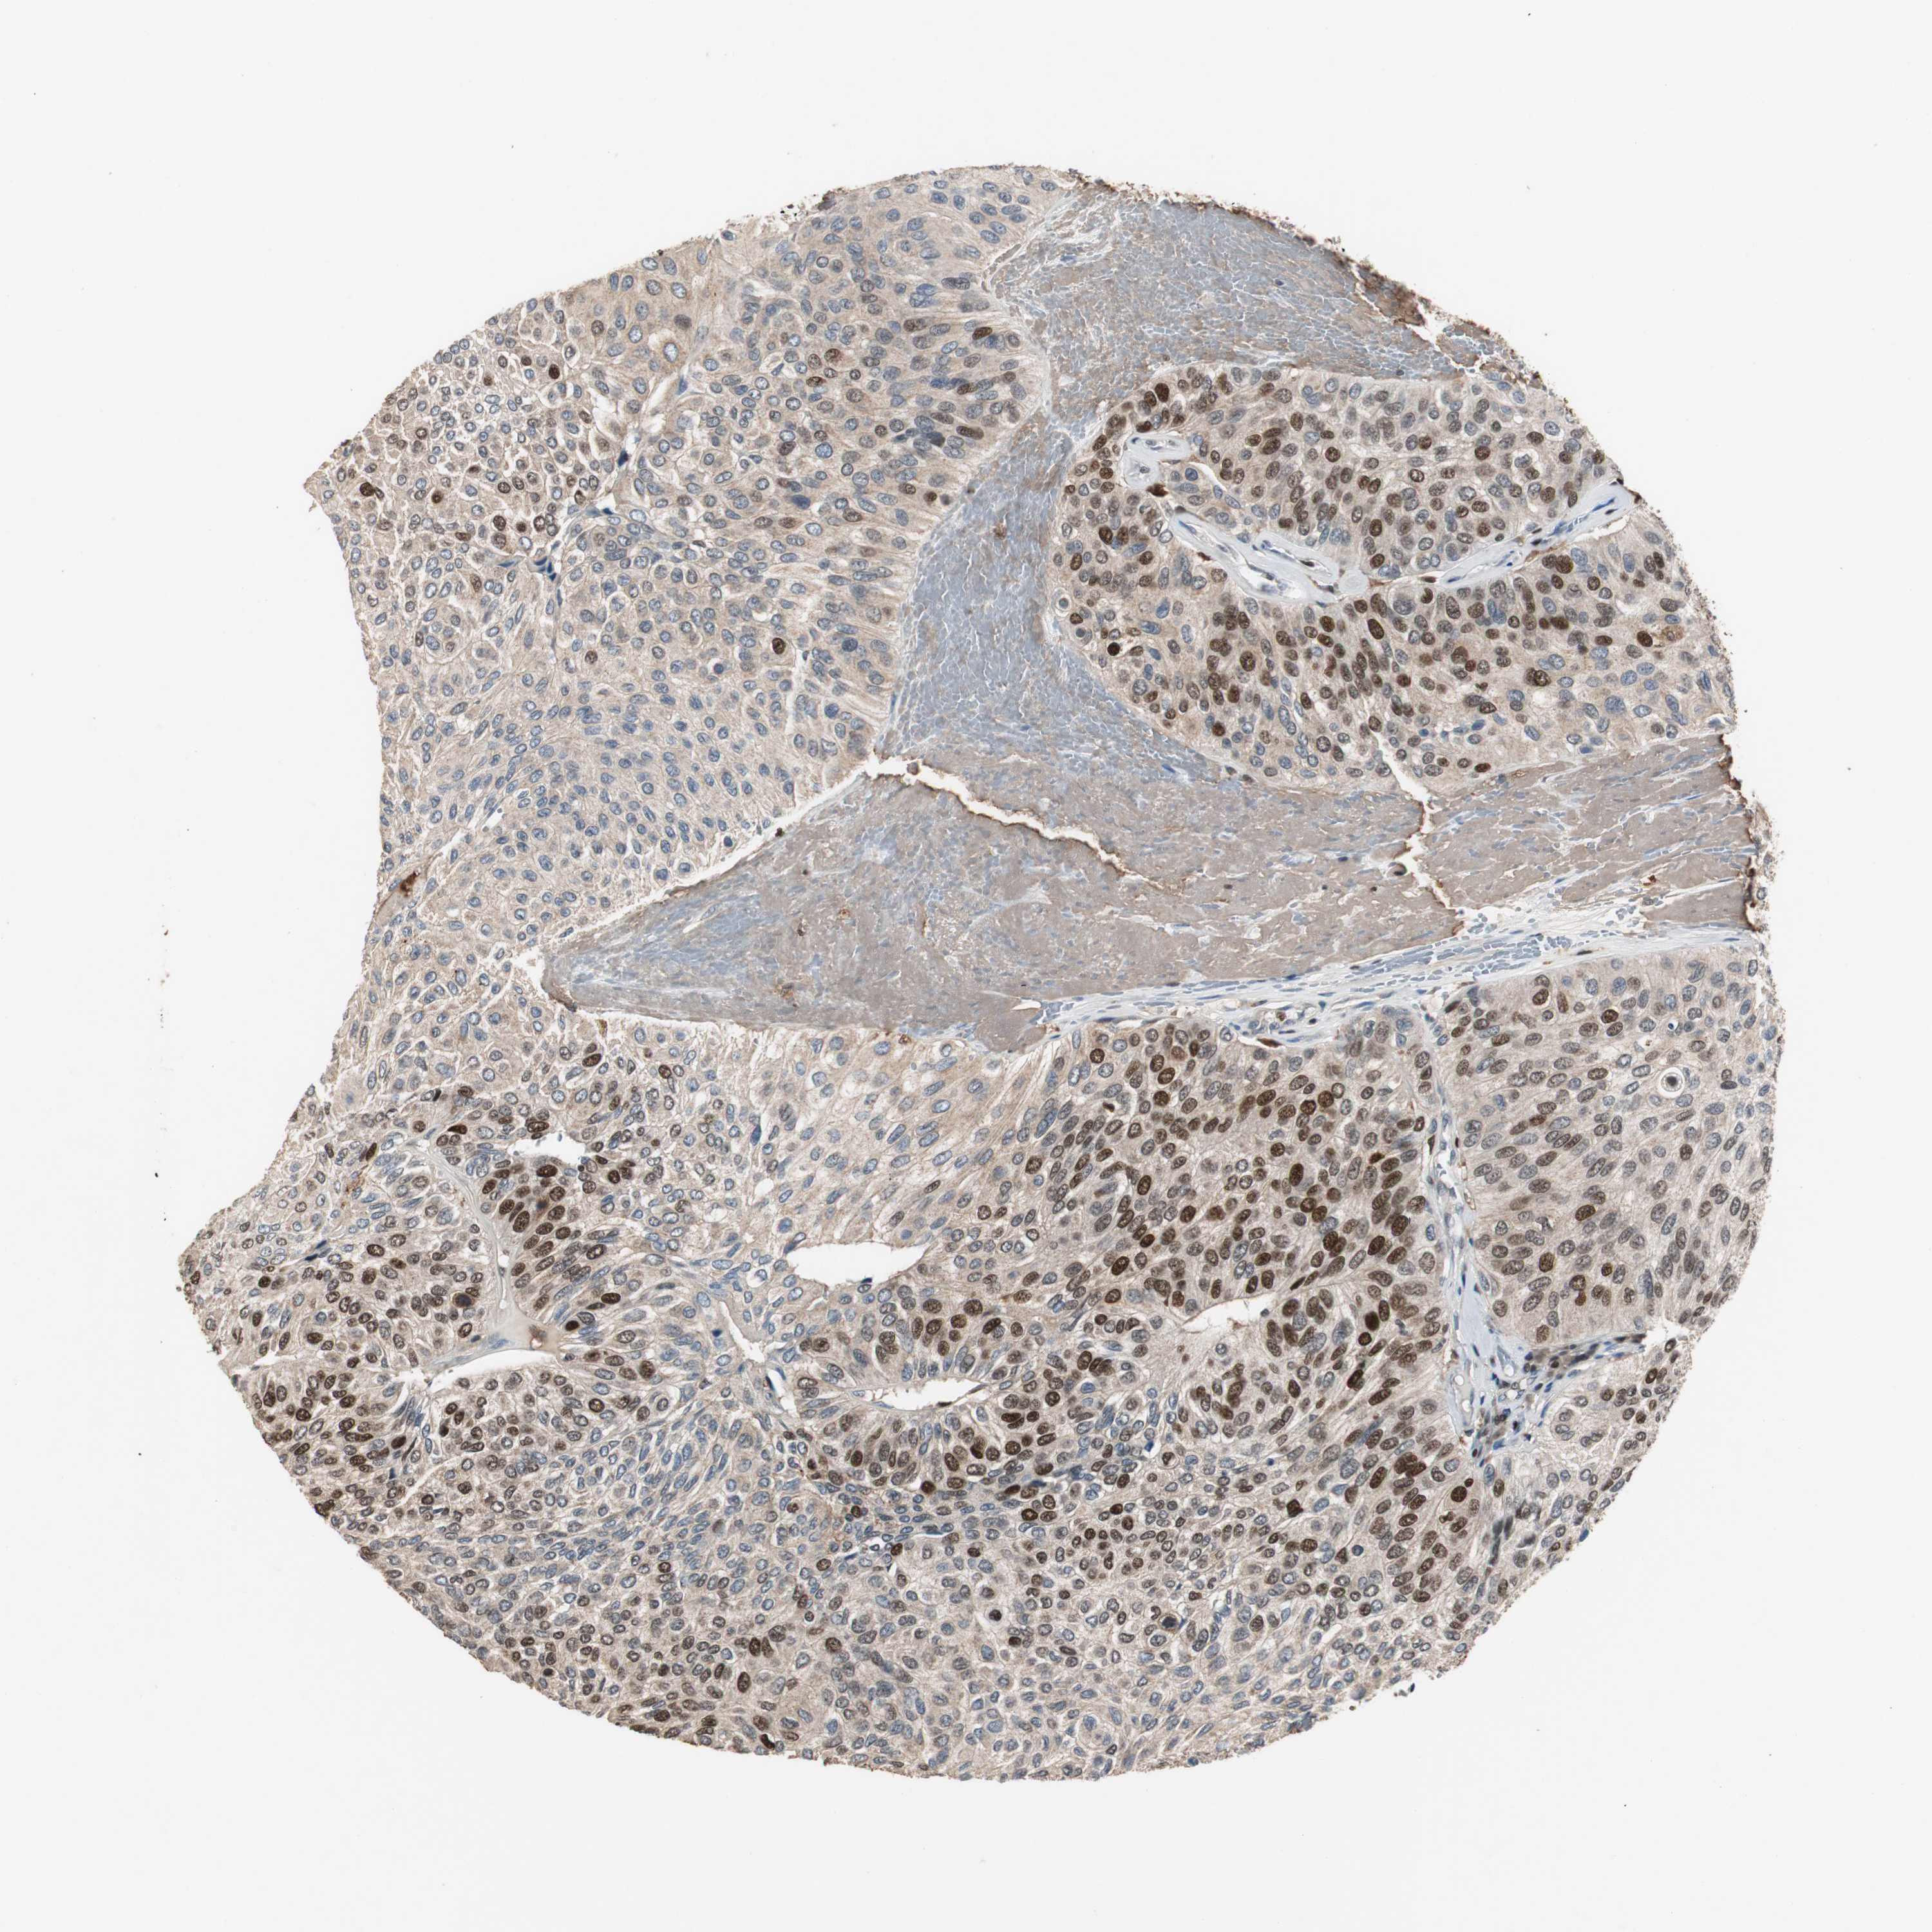

UROTHELIAL CANCER - Protein expressioni

A mouse-over function shows sample information and annotation data. Click on an image to view it in a full screen mode. Samples can be filtered based on level of antibody staining by selecting one or several of the following categories: high, medium, low and not detected. The assay and annotation is described here.

Note that samples used for immunohistochemistry by the Human Protein Atlas do not correspond to samples in the TCGA dataset.

Antibody stainingi

Antibody staining in the annotated cell types in the current human tissue is reported as not detected, low, medium, or high, based on conventional immunohistochemistry profiling in selected tissues. This score is based on the combination of the staining intensity and fraction of stained cells.

Each image is clickable and will lead to virtual microscopy that enables deeper exploration of all samples and also displays staining intensity scores, fraction scores and subcellular localization as well as patient and tissue information for each sample.

Antibody HPA006748

Antibody CAB002262

Staining

High

Medium

Low

Not detected

Intensity

Strong

Moderate

Weak

Negative

Quantity

>75%

75%-25%

<25%

None

Location

Nuclear

Cytoplasmic/membranous

Cytoplasmic/membranous,nuclear

Urothelial carcinoma, High grade